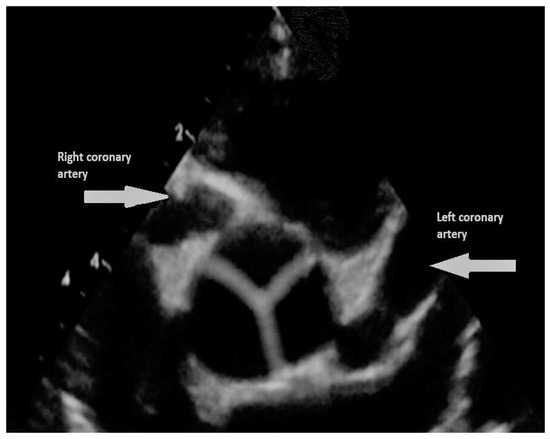

- Peña, E.; Nguyen, E.T.; Merchant, N.; Dennie, C. ALCAPA syndrome: Not just a pediatric disease. Radiographics 2009, 29, 553–565. [Google Scholar] [CrossRef]